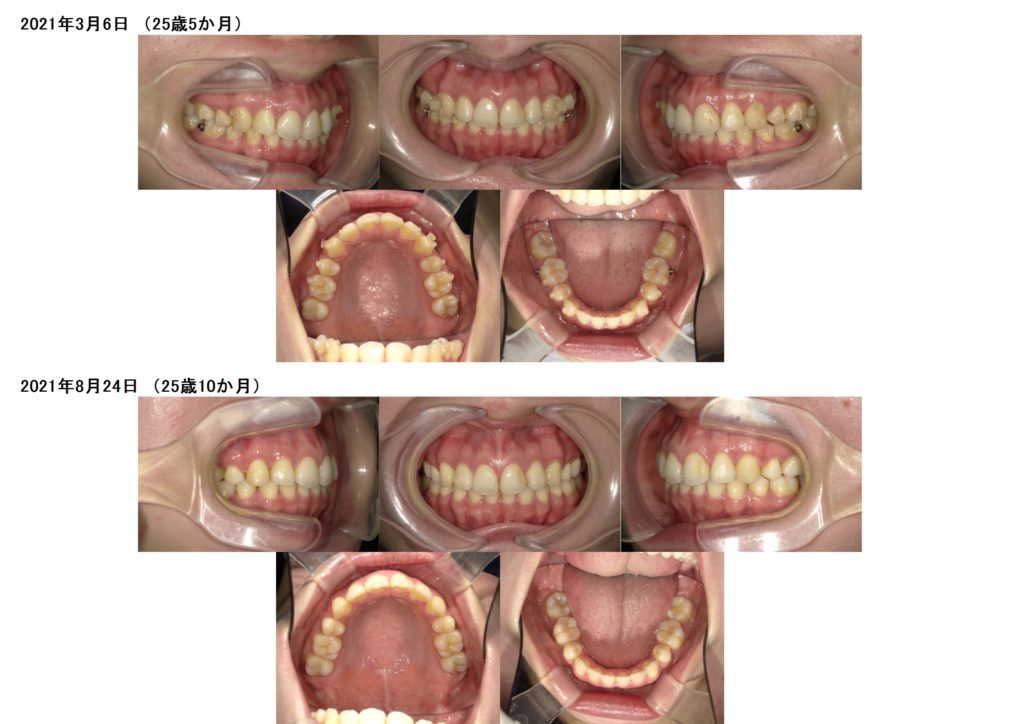

残っていた隙間もすべて閉じ、お口元が出ていたのも引っ込んでいるのが分かると思います。

あとは少し微調整します。

全体的にキュッと引き締まった感じがしますね☺

前歯の噛み合わせも変化しているのが写真を見比べてみると。。。。。

↑治療前、治療後の口腔内写真です。

お口元がとっても変化しているのが分かりますよね☆

上の口腔内写真が上あごのアーチの形が三角形の形をしていますよね。

これが、顎が狭く、お口元が突出している方の特徴です☆

このアーチを整えなければ、歯を抜いてスペースを確保してもとてもお口元が小さく、しぼんだ感じになってしまいます。